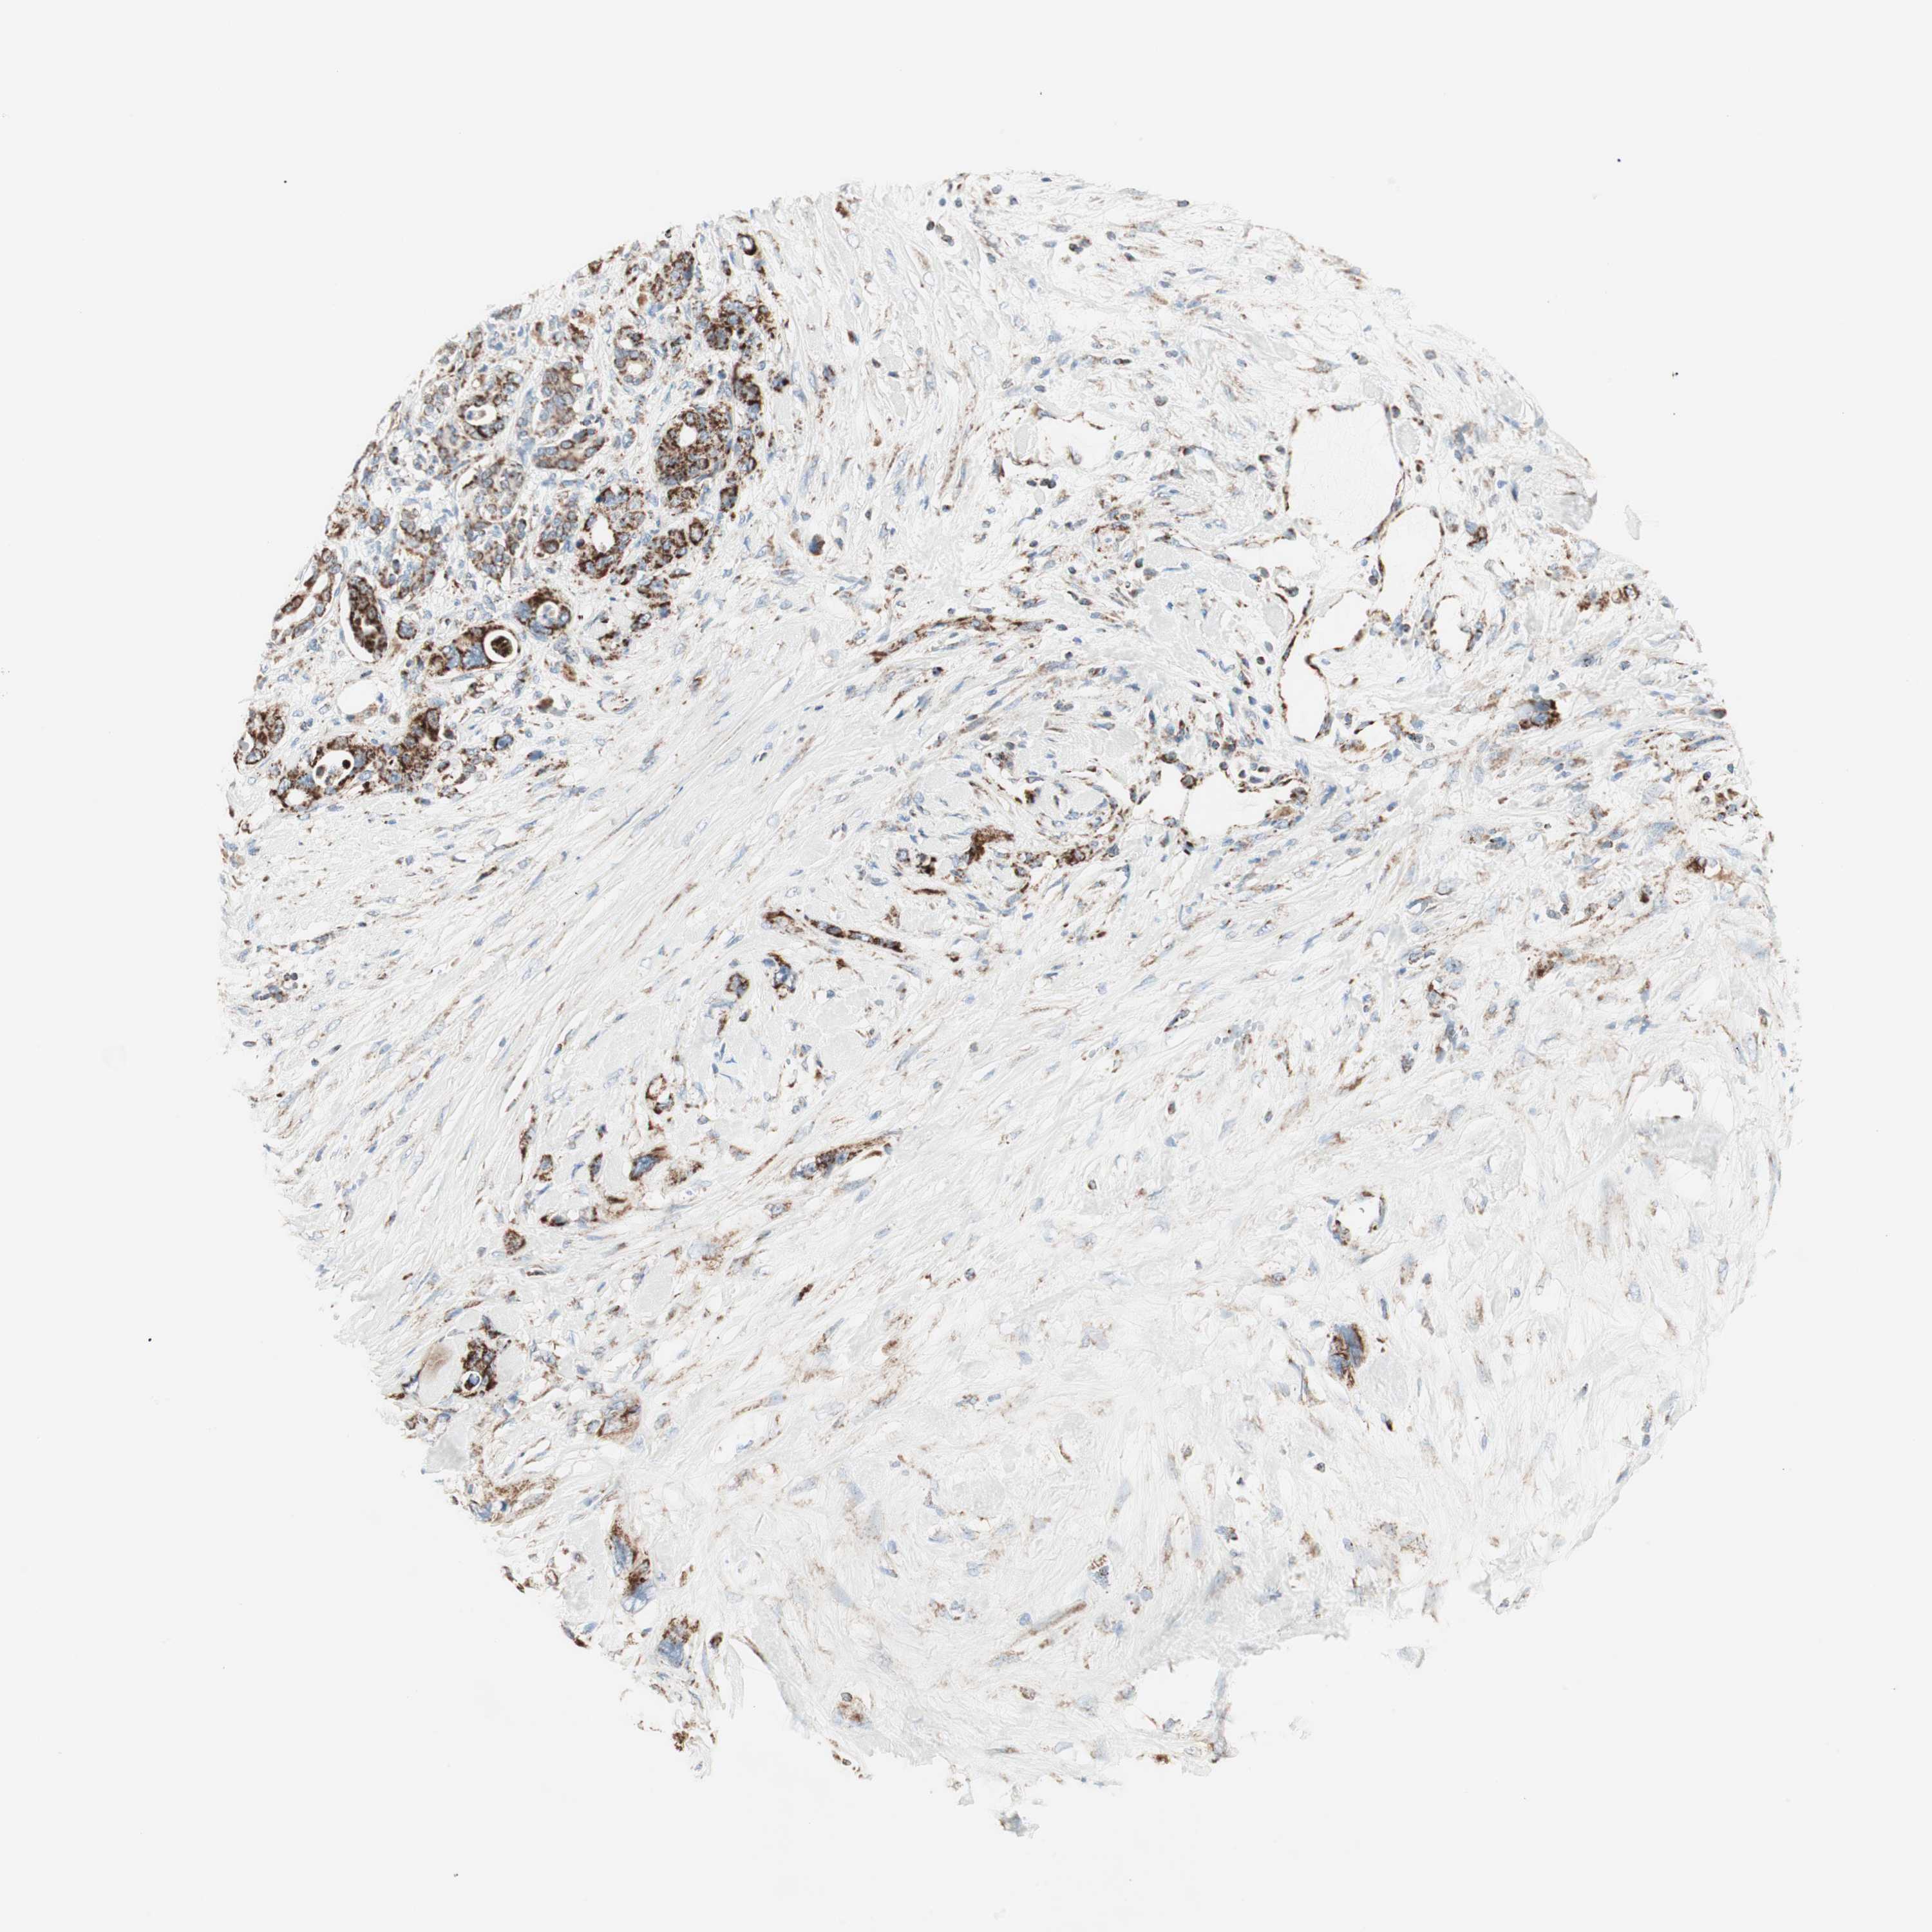

PANCREATIC CANCER - Protein expressioni

A mouse-over function shows sample information and annotation data. Click on an image to view it in a full screen mode. Samples can be filtered based on level of antibody staining by selecting one or several of the following categories: high, medium, low and not detected. The assay and annotation is described here.

Note that samples used for immunohistochemistry by the Human Protein Atlas do not correspond to samples in the TCGA dataset.

Antibody stainingi

Antibody staining in the annotated cell types in the current human tissue is reported as not detected, low, medium, or high, based on conventional immunohistochemistry profiling in selected tissues. This score is based on the combination of the staining intensity and fraction of stained cells.

Each image is clickable and will lead to virtual microscopy that enables deeper exploration of all samples and also displays staining intensity scores, fraction scores and subcellular localization as well as patient and tissue information for each sample.

Antibody HPA011562

Antibody CAB005585

Staining

High

Medium

Low

Not detected

Intensity

Strong

Moderate

Weak

Negative

Quantity

>75%

75%-25%

<25%

None

Location

Nuclear

Cytoplasmic/membranous

Cytoplasmic/membranous,nuclear

Adenocarcinoma, NOS

Adenocarcinoma, metastatic, NOS